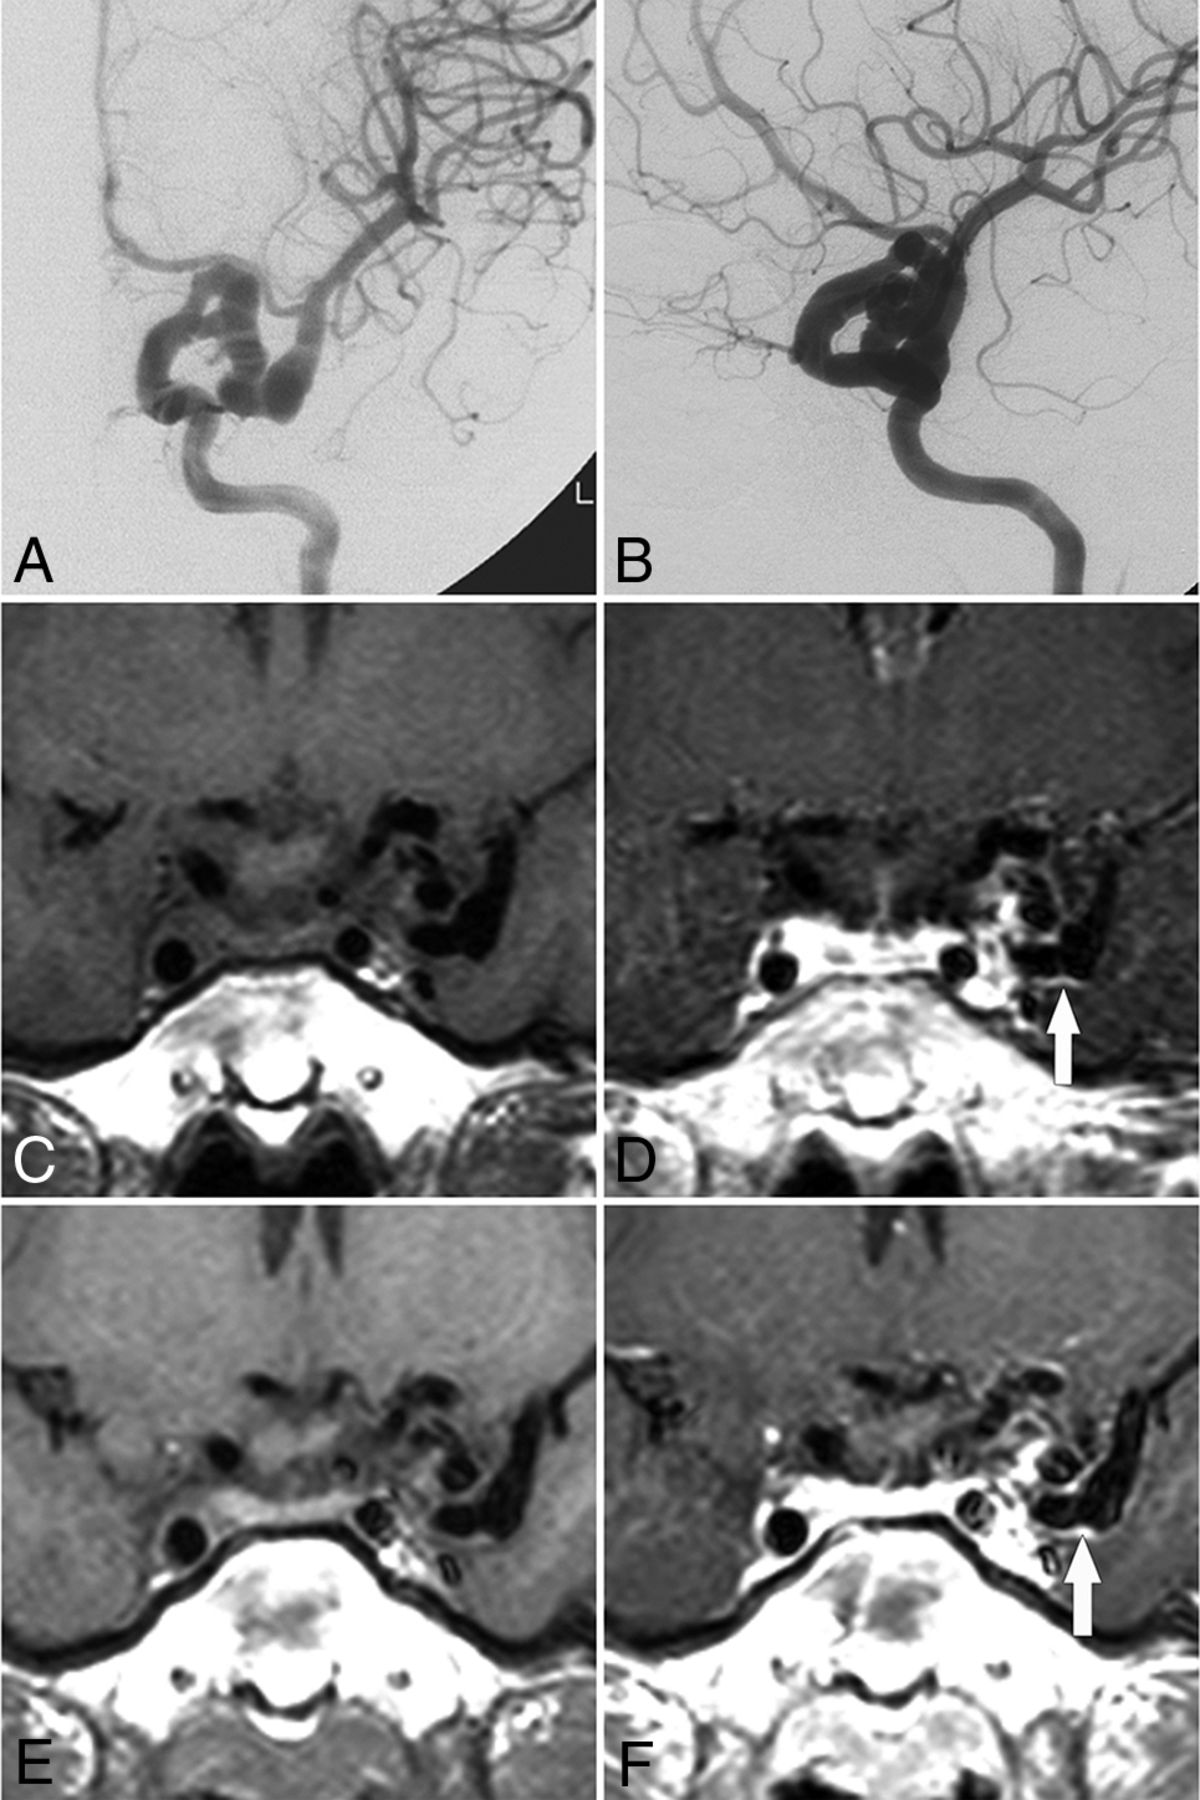

Ten patients underwent contrast-enhanced high-resolution MR imaging of the vessel wall, which detected enhancement in 6 patients with a mean age of 22.8 ± 13.2 years; the remaining 4 patients had a mean age of 57.0 ± 9.2 years (P < .001). One patient (patient 1, Fig 3) exhibited vessel wall enhancement at both 8 and 12 years of age, with no major change in the enhancement pattern. Vessel wall imaging revealed that the stenotic segment exhibited either an eccentric or concentric wall thickening (Fig 4) as well as a potential enhancement of the parent artery and aneurysm neck (Fig 5).

Evolution of vessel wall enhancement with aging in a patient with PHACE syndrome (patient 1, an 8-year-old girl). A and B, Left ICA angiography (anteroposterior and oblique views) reveals tortuosity in the left distal ICA with a small and long A1 segment. C and D, Noncontrast and contrast-enhanced vessel wall imaging at 8 years of age demonstrates vessel wall enhancement and slight vessel wall thickening (arrow in D). E and F, Vessel wall imaging at 12 years of age shows a similar vessel wall enhancement pattern (arrow in F).

Vessel wall enhancement at the stenotic segment in a patient with possible PHACE syndrome (patient 5, a 23-year-old woman). A and B, Left ICA angiography and TOF-MRA reveal dolichoectasia of the left distal ICA, left PcomA (arrow), and left AchoA (curved arrow). C–E, Section images reveal the vessel wall thickening and enhancing patterns of each corresponding stenotic segment (arrowheads indicate the vessel wall thickening and asterisks indicate vessel lumen; C, sagittal plane; D and E, axial plane). P indicates posterior; R, right.